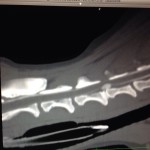

La TAC, o per esteso Tomografia Assiale computerizzata a raggi X, è una metodica di diagnostica per immagini avanzata, che sfrutta i principi fisici dei raggi X associandoli a complesse elaborazioni digitali, in modo da ottenere immagini ad elevata risoluzione di un determinato segmento corporeo.

Le immagini vengono acquisite sul piano trasversale e poi, attraverso un software di ricostruzione, possono essere visualizzate ed esaminate nelle tre dimensioni spaziali (ricostruzioni MPR)

Neurologia: la TAC è una metodica che nasce proprio come studio per la valutazione delle patologie endocraniche e ancora oggi permette di identificare molte lesioni encefaliche (soprattutto di natura neoplastica) con estrema precisione. E’, inoltre, da sola o associata a indagine mielografica, una metodica di studio veloce e estremamente attendibile nell’identificazione di patologie della colonna vertebrale , come ad esempio le ernie discali o altre patologie compressive a carico del midollo spinale, oltre a patologie congenite e di natura TRAUMATICA.

Ortopedia: Completamento degli studi radiografici qualora si voglia identificare con esattezza il tipo di lesione sospettata. Ad esempio è un ausilio estremamente importante nelle patologie displasiche del gomito perché permette l’identificazioni di eventuali frammenti liberi endoarticolari in corso di frammentazione del processo coronoideo mediale dell’ulna (FCP) o di lesioni a carico della superificie articolare omerale (osteocondrite dissecante/Kissing lesions).